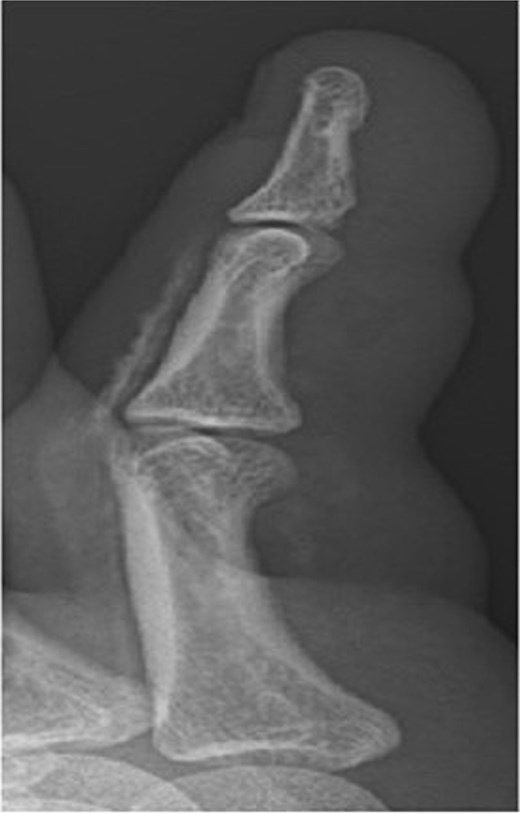

Initial presentation (Fig. 7) with accompanying X-ray (Fig. 8). Final image shows patients digit when he represented 2 months after original insult with a swollen finger and pus exudate (Fig. 9).

X-ray image of patient three showing injected material into surface of his digit, more obvious in the proximal portion.

Patients three’s digit when he represented 2 months after original insult with a swollen finger in a flexed position and pus exudate.